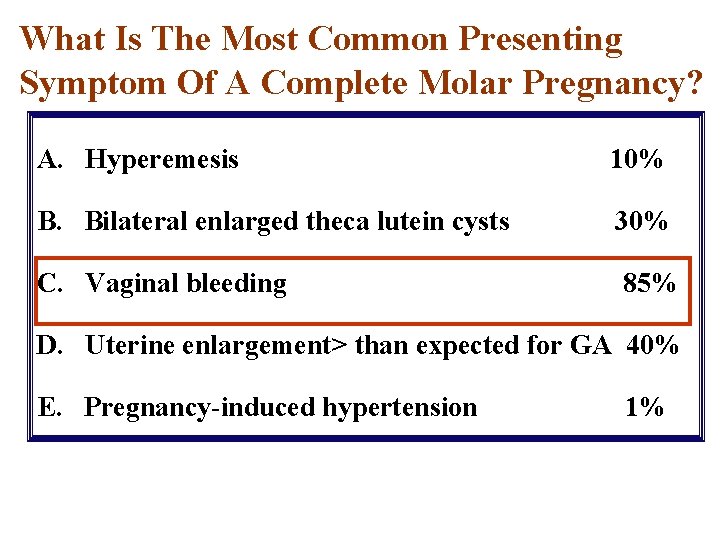

What Is The Most Common Presenting Symptom Of A Complete Molar Pregnancy? A. Hyperemesis B. Bilateral enlarged theca lutein cysts C. Vaginal bleeding D. Uterine enlargement> than expected for GA E. Pregnancy-induced hypertension

What Is The Most Common Presenting Symptom Of A Complete Molar Pregnancy? A. Hyperemesis 10% B. Bilateral enlarged theca lutein cysts 30% C. Vaginal bleeding 85% D. Uterine enlargement> than expected for GA 40% E. Pregnancy-induced hypertension 1%